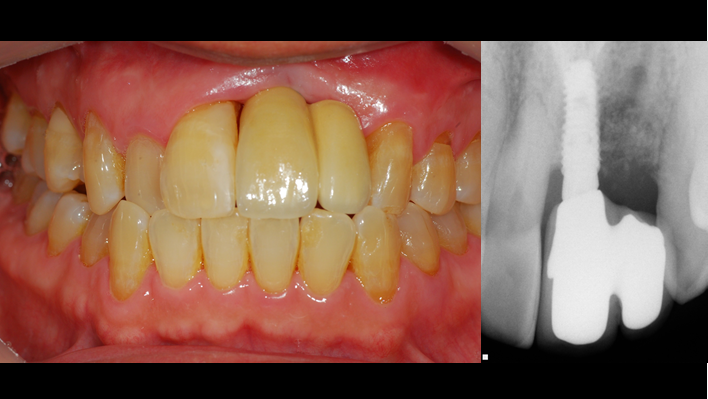

“Achieving a clean surface is the key to treating peri-implantitis!Using a titanium or NiTi brush for the decontamination process along with proper GBR can successfully restore the peri-implant environment. ”

Clinical case: Peri-implantitis treatment case using titanium or NiTi brush

- Courtesy of Dr. Dae-Hee Lee, South Korea -

Dr. Dae-Hee Lee,Maxillary Anterior,Peri-implantitis,Bone regeneration,Aesthetic zone,#21,#22,GBR,Titanium Brush Set